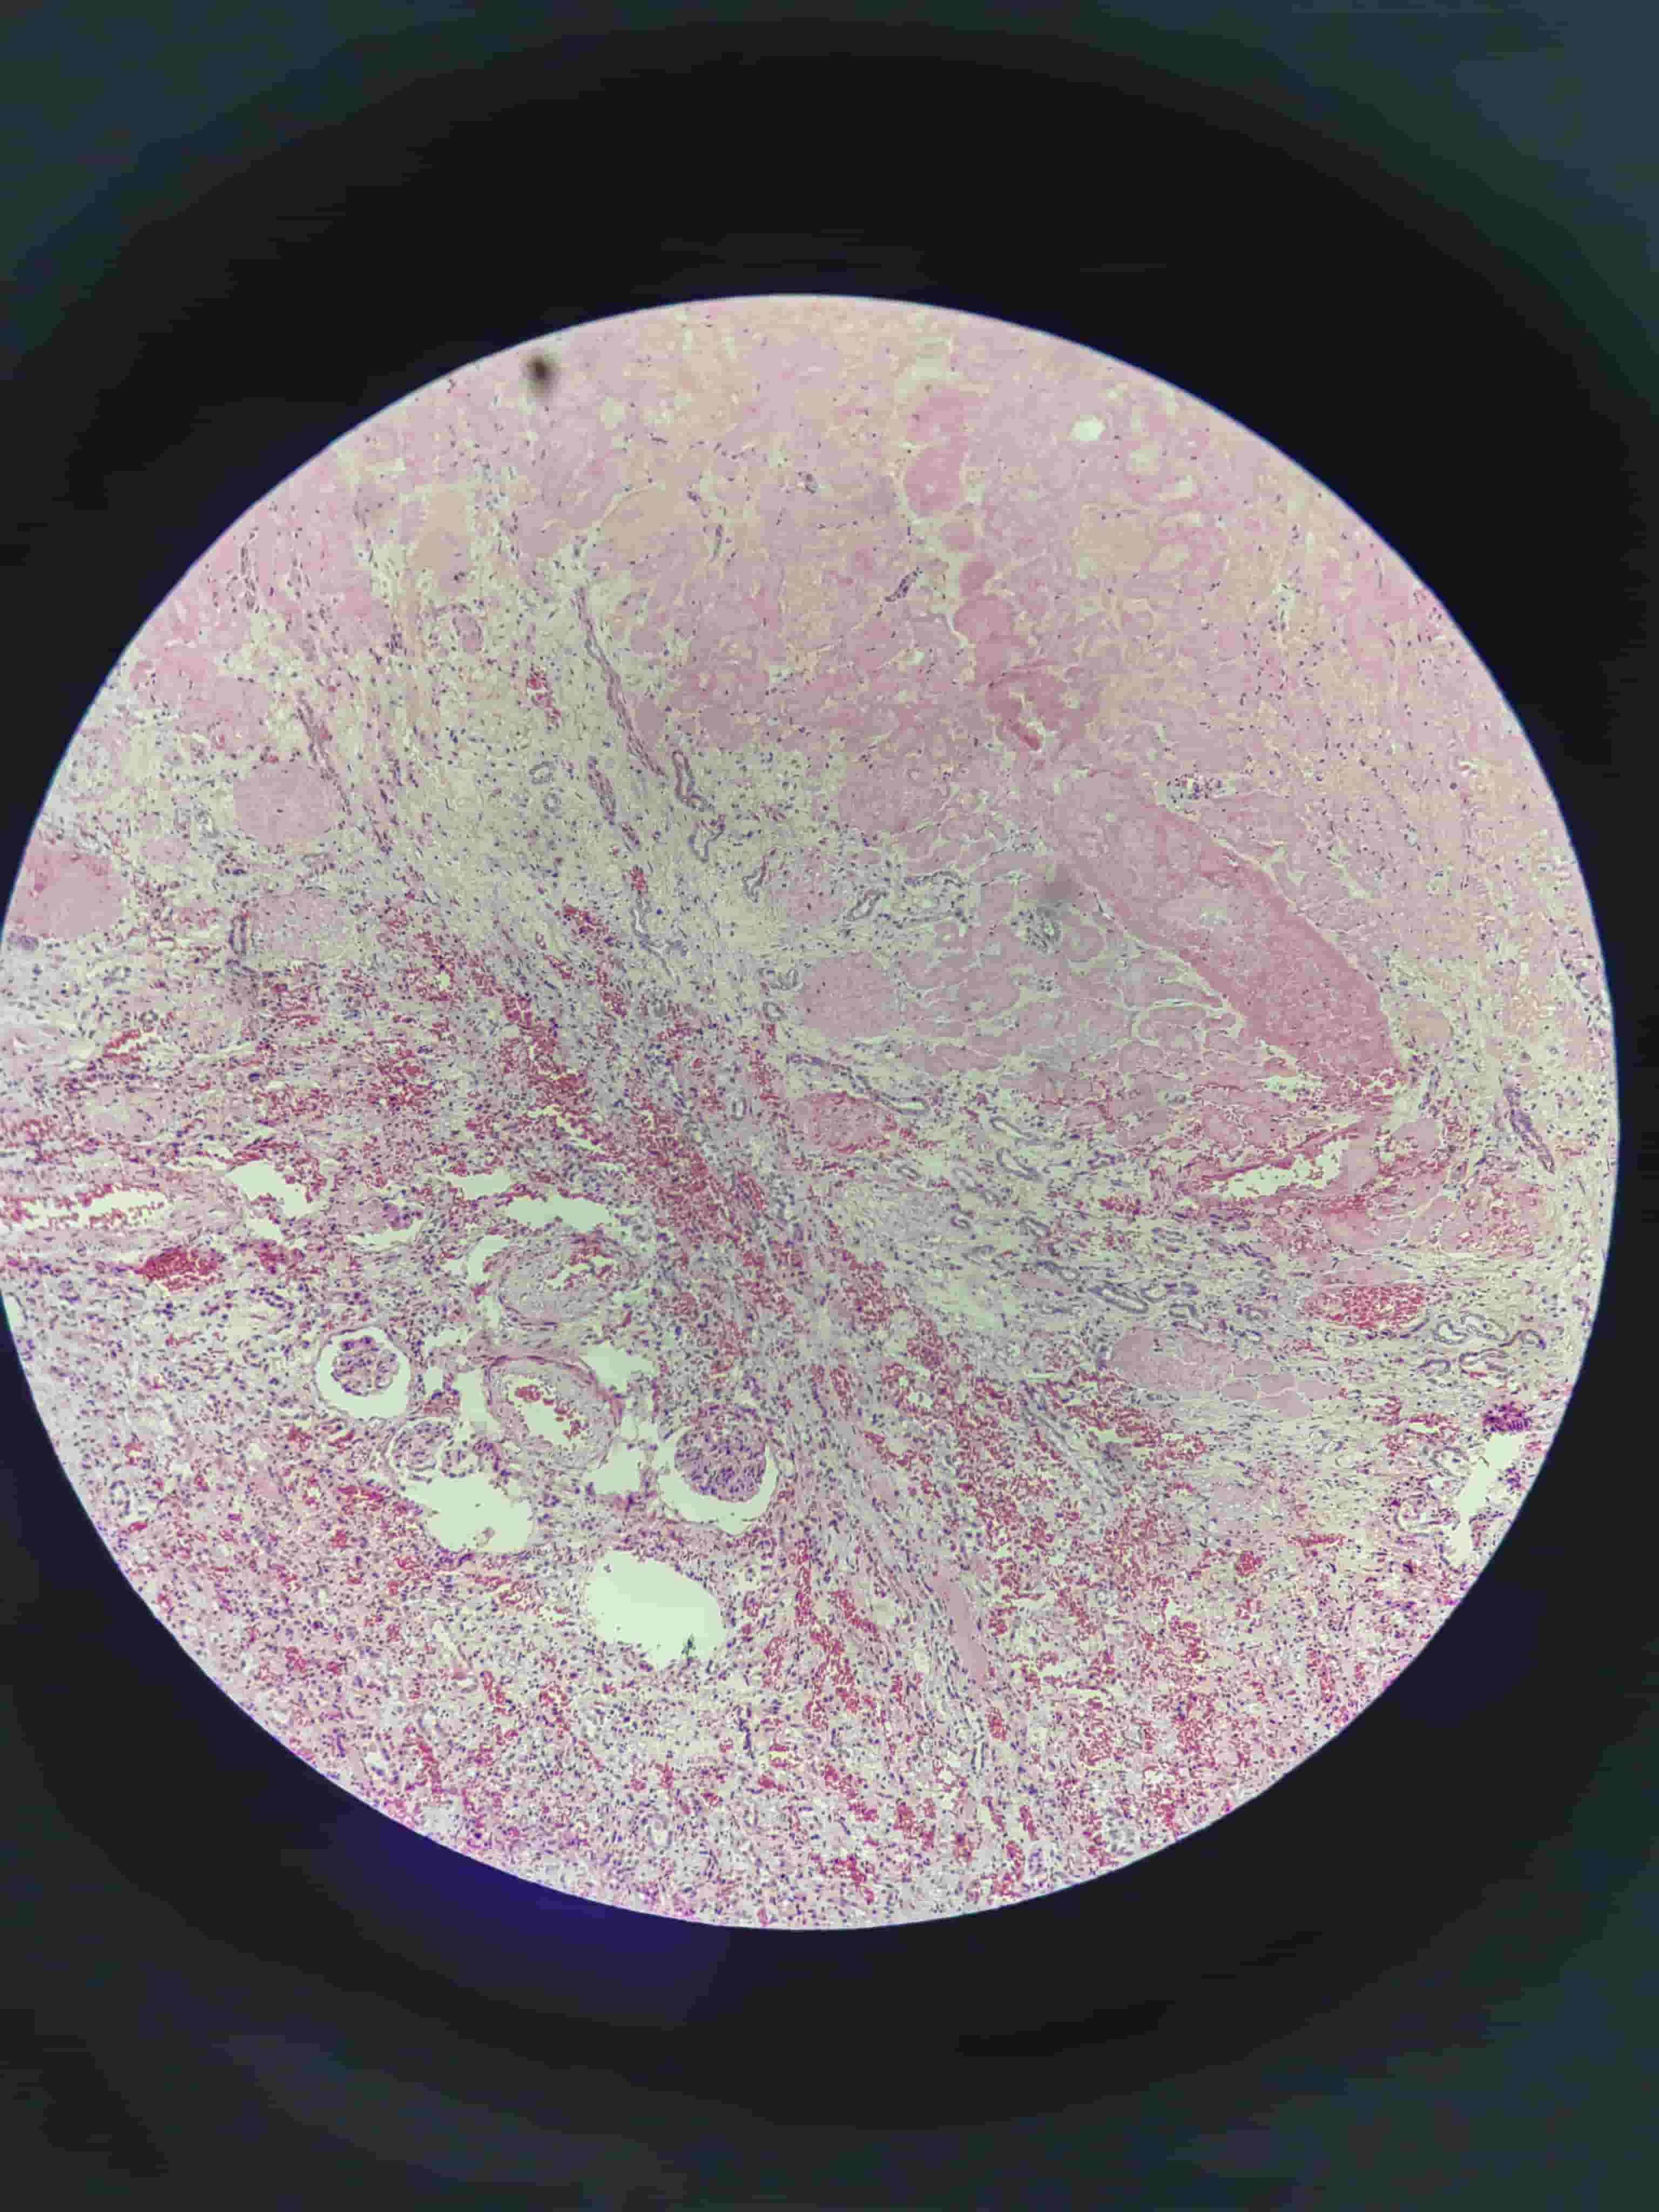

肉芽组织

- 毛细血管、成纤维细胞

- 炎细胞浸润